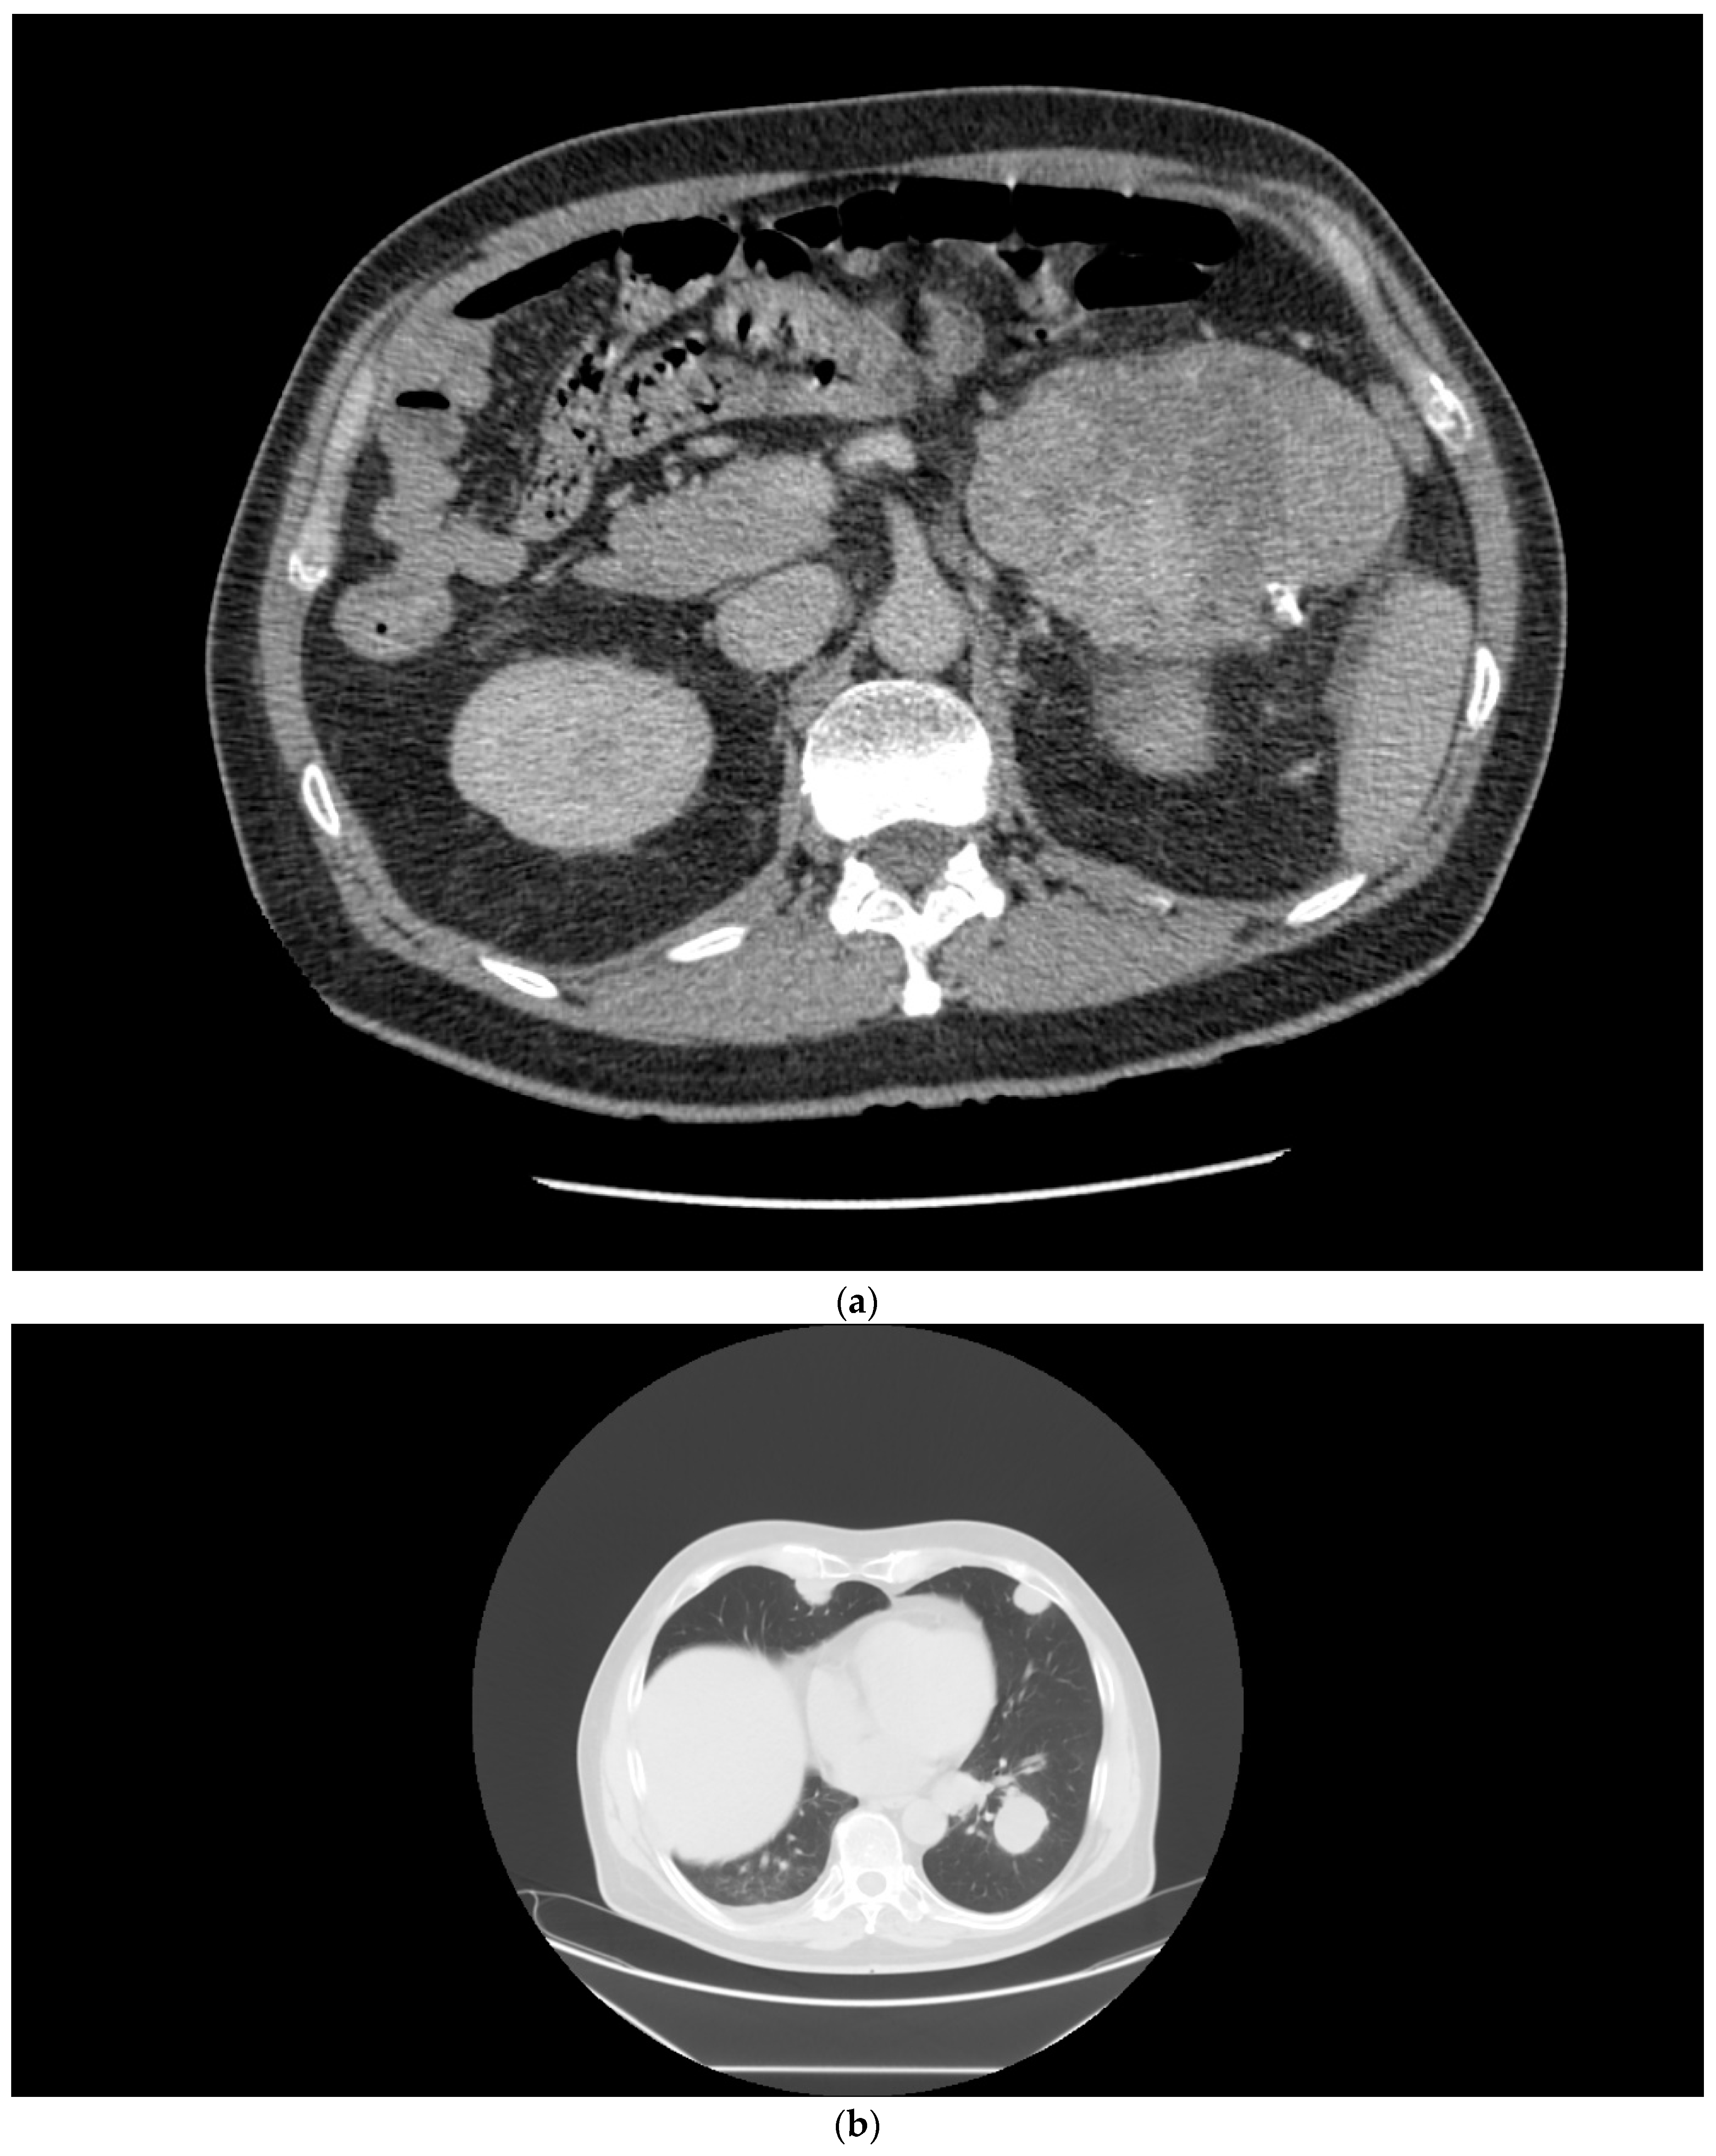

A 58-year-old male patient presented in November 2014 with a left renal mass and bulky retroperitoneal lymphadenopathy (Figure 2a). The patient had a short history of arterial hypertension and sinus tachycardia. Laboratory examinations at the time of diagnosis showed anemia, thrombocytosis, neutrophilia, and alanine aminotransferase (ALT) and aspartate aminotransferase (AST) CTCAE grade 1 elevation. The patient had the tumor removed in November 2014, but the surgery was only cytoreductive and not radical, leaving a left residual mass in the retroperitoneum. Histological examination revealed sRCC pT3pN1M0. A CT scan two months after surgery showed multiple lung metastases, 3 cm in size (Figure 2b), and a large mass in the retroperitoneum (Figure 2c). The patient had a poor prognosis score according to IMDC (anemia, neutrophilia, thrombocytosis, KPS, and interval to therapy initiation). The laboratory parameters of liver function improved after surgery and were within normal range. In March 2015, the patient was enrolled in the CheckMate 214 trial and received the combination therapy of nivolumab plus ipilimumab at a standard dose for four cycles, then continued with nivolumab monotherapy (3 mg/kg) every two weeks, achieving major partial response on CT examination within two months (Figure 2d). Soon after therapy initiation, the patient felt relieved, and his blood count was normalized. The patient continued with the therapy until October 2021, when the therapy was permanently stopped due to grade 3 ALT and AST elevation. Intravenous methylprednisone 1 mg/kg was immediately initiated. Liver tests gradually returned to normal, and all clinical symptoms accompanying the course of therapy that the patient did not consider, including grade 1 diarrhea, grade 2 insomnia, and grade 1 joint pain, disappeared. The patient continues to be followed. At the last visit in May 2022, he was without evidence of disease activity.

Figure 2.

(a) Patient 2, pretreatment CT of the renal tumor. (b) Patient 2, pretreatment CT of the chest demonstrating lung metastases. (c) Patient 2, a large mass in the retroperitoneum. (d) Patient 2, major partial response after the combination regimen of ipilimumab with nivolumab.